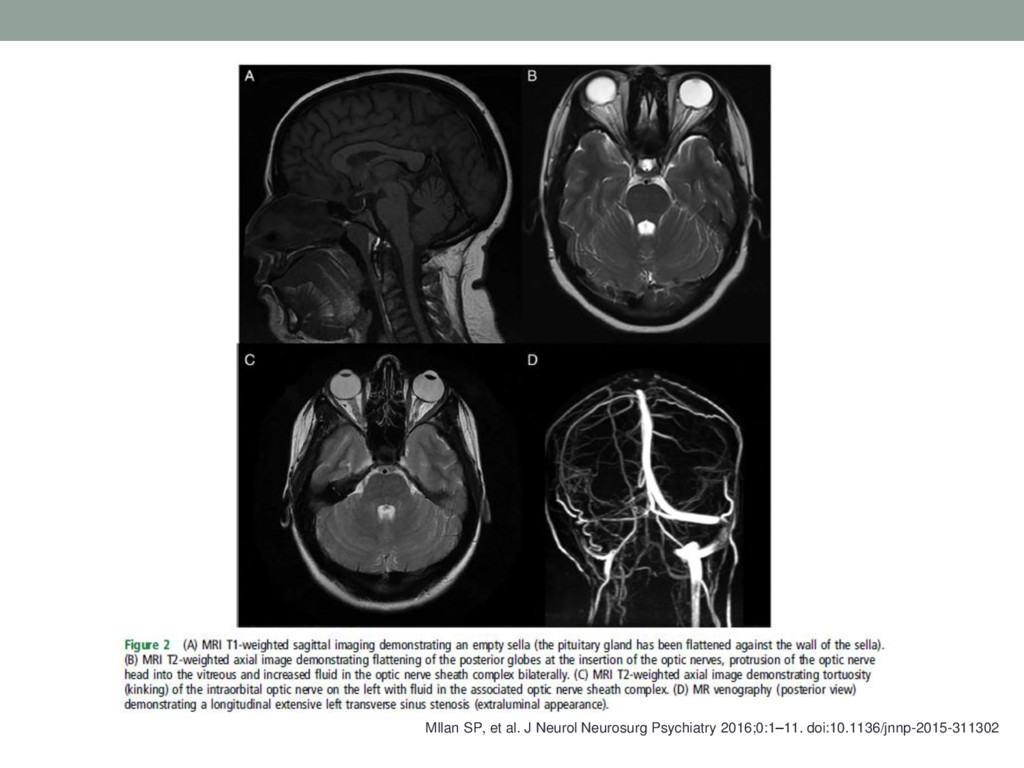

17. « L’Hypertension intracrânienne idiopathique» • Evolving evidence in adult idiopathic

intracranial hypertension: pathophysiology and management • Mollan SP, et al. J Neurol Neurosurg Psychiatry 2016;0:1–11 • L.Suchet

Psychiatry 2016;0:1–11. doi:10.1136/jnnp-2015-311302 • Femme de 20 à 40 ans obèse • 25% des cas = BAV définitive, 1 à 2% des cas/an deviennent aveugles • Doublement cas entre 1997 et 2002 en GB, triplement aux USA entre 1990 et 2006 (dérivations +320%) • Incidence 28/100000/an quand stratifiée sexe/poids/âge, entre 1 et 3/100000/an sinon. • Le premier cas d’HII (méningite séreuse à l’époque) rapporté dans les années 1890s par l’allemand Henrich Quincke, avec l’utilisation de la première PL. • Nonne a décrit une série de cas similaires à Dandy d’élévation de la pression du LCR sans tumeur (pseudotumour cerebri). • Evolution importante des critères. • Certains patients ont des évolutions légères chroniques.